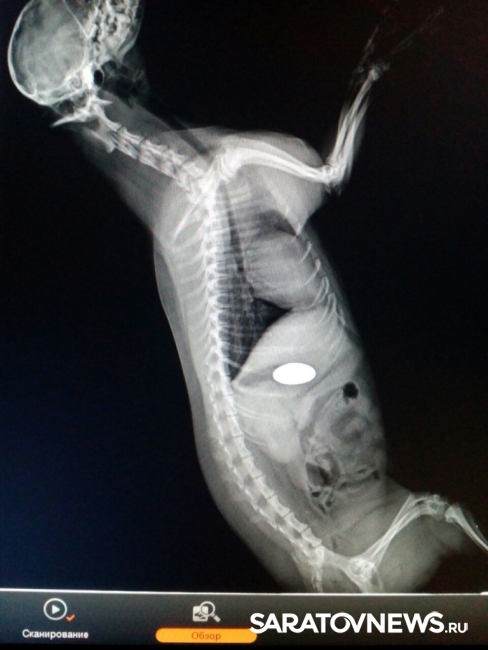

Специалисты саратовской ветлечебницы №1 спасли пса, проглотившего пуговицу. Как сообщает управление ветеринарии правительства Саратовской области, помощь потребовалась йоркширскому терьеру Жуже.

"Животное отказывалось от пищи, было вялым. Ветеринарные специалисты с помощью рентгена определили, что собака проглотила пуговицу, и она находится в желудке", - сообщают ветеринары.

Двухсантиметровую пуговицу из терьера достали, сейчас Жужа успешно проходит восстановительный период.